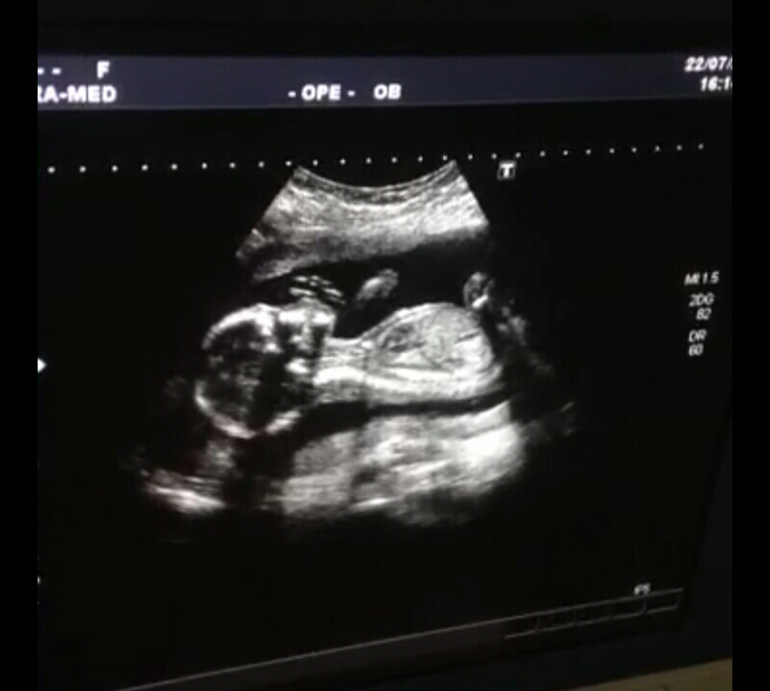

Все хорошо с ним) лежал икал, пузыри пускал) нам распечатали 5 фото) все показали) сказали что плод большой весь в папу

Ручкой за носик хватался) и ножки показали)

Поздравляю!! :) Я всегда думала, что снимки УЗИ у всех одинаковые, но смотрю на ваши фотографии, все-таки нет, видно очертания личика) У нас носик другой и губки) прикольно)